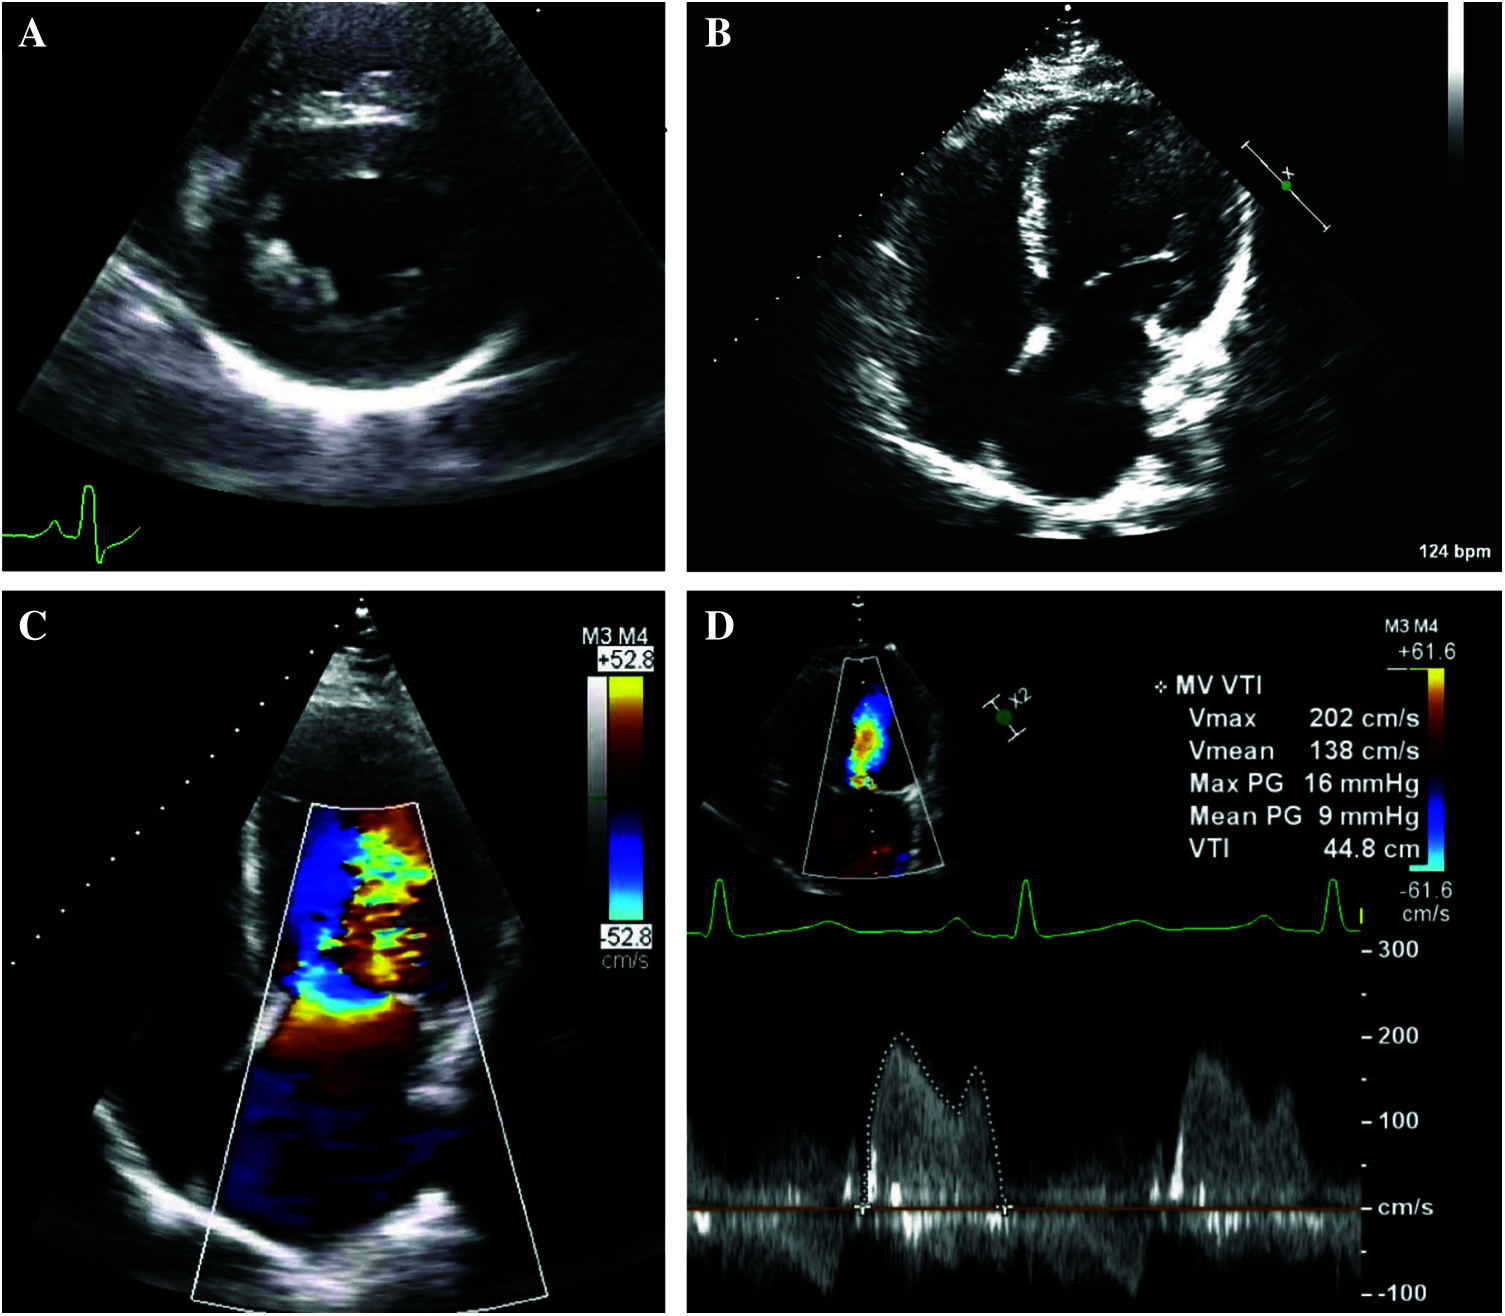

Figure 4: Echocardiography of patient 4 demonstrating her stenotic parachute mitral valve during the third trimester of gestation

Panel A: A parasternal short axis image revealing a dominant posteromedial papillary muscle, which is commonly noted in patients with a parachute mitral valve.

Panel B: An apical image revealing a parachute mitral valve with the chordae tendinae attached to a single papillary muscle.

Panel C: Color flow imaging revealing flow acceleration across the stenotic parachute mitral valve.

Panel D: Doppler echocardiography of the stenotic parachute mitral valve showing a diastolic mean pressure gradient of 10 mmHg (heart rate 77 bpm).